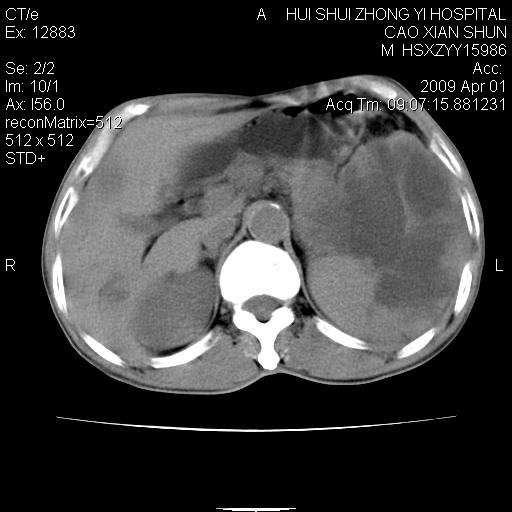

以下是引用随光逐影在2009-4-1 14:23:00的发言:[br]肝、脾多发低密度占位性病变,性质待定(不排除转移瘤可能);建议行进一步检查。

以下是引用liaoqiang在2009-4-1 15:53:00的发言:[br]考虑脾脏肿瘤或胰尾部肿瘤伴肝转移。建议增强。

以下是引用ydx_74在2009-4-1 15:18:00的发言:[br]肝、脾多发低密度占位性病变,考虑转移瘤或淋巴瘤